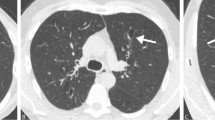

The relationship between COPD diagnosed by spirometry and emphysema severity reported by LDCT was poor (Weighted Kappa =0.16) (Fig. 1). Among 1378 individuals having no COPD by spirometry, 361 (26.2%) had mild or worse emphysema by LDCT report. By contrast, among 97 individuals with severe or very severe disease by spirometry, 38 (39.2%) had no or trivial COPD by LDCT report.

CT changes of emphysema were reported in just over half of individuals (50.9%) not having COPD according to spirometry. Previous investigators have found that a portion of individuals diagnosed with COPD by CT do not meet criteria by spirometry [46, 47]. In a large population with respiratory symptoms not meeting spirometry criteria, Regan et al. found that 42.3% had CT evidence of either emphysema (24.0%) or airway thickening (30.7%) [44]. The reason for this apparent mismatch between radiologic and spirometric findings is not clear. Given that other studies have made similar findings, there is likely a population for whom the changes observed on CT are physiologically insufficient to make a formal diagnosis of COPD possible. This is consistent with data which suggests that early radiologic changes presage later changes in spirometry [48]. Certainly, the extent to which CT changes are detected in individuals without COPD by spirometry will depend on which CT changes are sought, as exemplified by the work of Regan et al. [44].

In our population, the relationship between severity of COPD by LDCT as compared to FEV1 was poor, although LDCT did contribute to COPD prediction in our model. By comparison, in another low-dose CT screening population, Omori et al. found a modest association between a visual, semi-quantitative emphysema score and spirometry findings [47]. While data from the COPDGene study showed that subjective readings of emphysema in standard dose CT imaging correlated well with quantitative results and spirometry [49], other data suggests radiologists are more likely to overestimate COPD than would a CT densitometry algorithm [28].